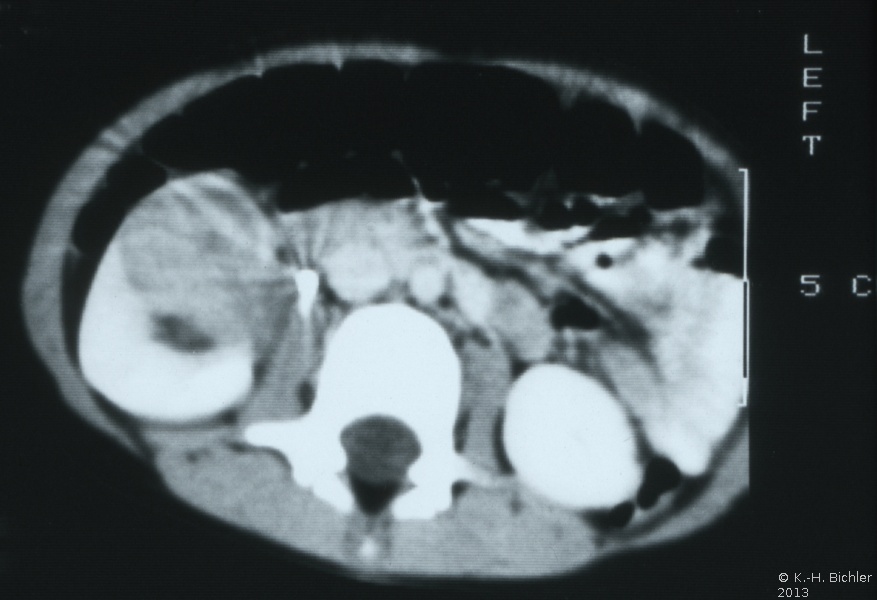

Die Computertomographie zur Bestimmung der Tumorausdehnung, zum Ausschluss einer zystischen Nierenfehlbildung (Differentialdiagnose) und zur Suche nach einem eventuellen kontralateralen Nierentumorbefall von Interesse. Außerdem dient das CT zur Flankierung der Chemotherapie (Ergebniskontrolle) (Abbildung 7,8,9).

(Die Abbildungen 7-8 wurden uns freundlicherweise von Herrn Dr. med. Günter Antes, Kempten überlassen)